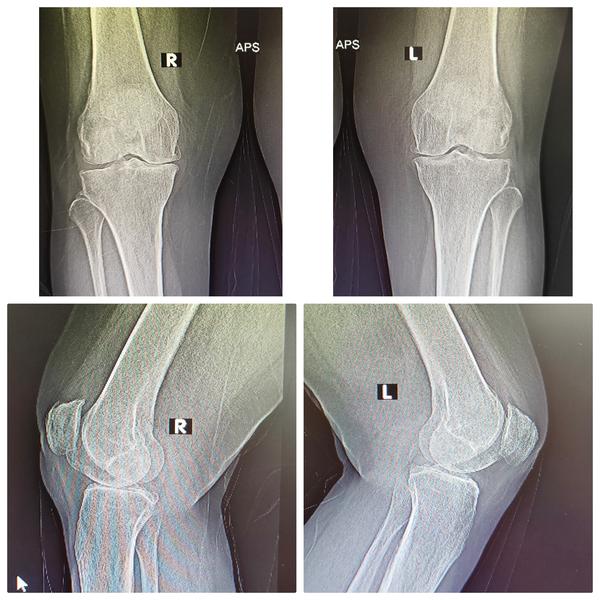

Joint reconstruction surgery is a valuable option for individuals who are experiencing joint pain and dysfunction due to various factors, including aging, wear-and-tear, or injuries. When less invasive treatments like injections and physical therapy are no longer effective, joint reconstruction surgery can provide relief and improve the quality of life.Total Knee Replacement (TKR):Total Hip Replacement (THR)Total Shoulder Replacement (TSR):Total Ankle Replacement (TAR):Elbow Replacement Surgery:Hand and Wrist Joint Reconstruction

Robotic Knee Replacement Surgery is an advanced surgical technique that utilizes robotic assistance during knee replacement surgery to improve precision and outcomes. Here's how it works:Preoperative Planning: Before the surgery, the surgeon uses advanced imaging techniques, such as CT scans or MRI, to create a 3D model of the patient's knee. This detailed preoperative planning allows for a customized surgical approach.Navigation Assistance: During the surgery, the surgeon uses a robotic system that includes a computer and a robotic arm. The 3D model of the patient's knee is loaded into the computer, providing a real-time, high-resolution view of the knee joint.Surgical Precision: The robotic arm is controlled by the surgeon but offers enhanced precision and control. It assists the surgeon in making precise cuts in the bone and accurately positioning the implant components.Feedback and Safety Measures: The robotic system provides real-time feedback to the surgeon, ensuring that the planned cuts and implant placements are executed accurately. It can also prevent the surgeon from making any movements that could potentially damage surrounding tissues.Customized Approach: Robotic knee replacement allows for a highly customized approach, taking into account the patient's unique anatomy and the extent of joint damage. This can lead to a better fit and alignment of the artificial knee components.Less Invasive: Robotic-assisted surgery often requires smaller incisions than traditional knee replacement surgery. This can lead to less tissue damage, reduced pain, and a quicker recovery.Faster Recovery: Patients who undergo robotic knee replacement surgery may experience a faster recovery and shorter hospital stays compared to traditional surgery.Improved Long-Term Outcomes: The precise alignment and positioning of the knee implant components can contribute to improved long-term outcomes, including better joint function and longevity of the implant.